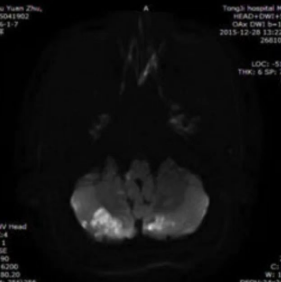

此外,PFO-AS的影像学特征显赫,具体明白为:①后轮回更易受累;②皮质或皮质下梗死多见;③病灶景色各样:梗死灶既可呈现为单发,也可为多发气象;④病灶尺寸偏小。

图5 PFO-AS影像学(图源:作家)